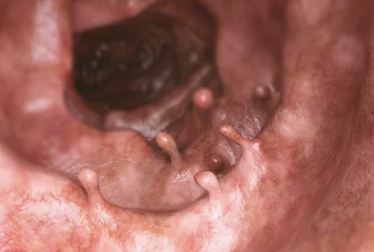

| 대장내시경 | 대장 전체를 관찰하며 이상 소견 즉시 조직 검사 가능 |

| 용종 발견 이력 | 특히 선종성 용종 |